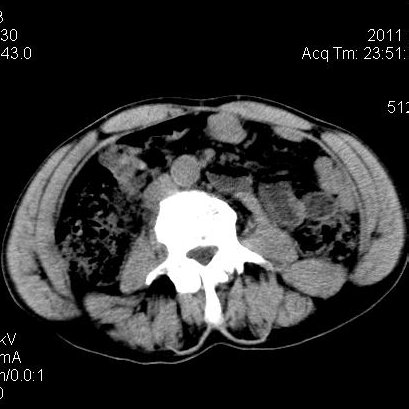

肝左叶发育异常

男性,55岁,骑摩托车摔倒后入院,自述右上腹疼痛

[backcolor=#FF0000]第一次诊断的时候也是这么肯定,可是床旁超声检查并没有发现明显异常,而且患者的一般症状都良好。还好临床只是保守治疗,没有立即手术,第二次复查的时候没有一点变化,又做了MRI检查,没有血肿,

这是一例肝左叶发育异常的,很个性吧~[/backcolor]